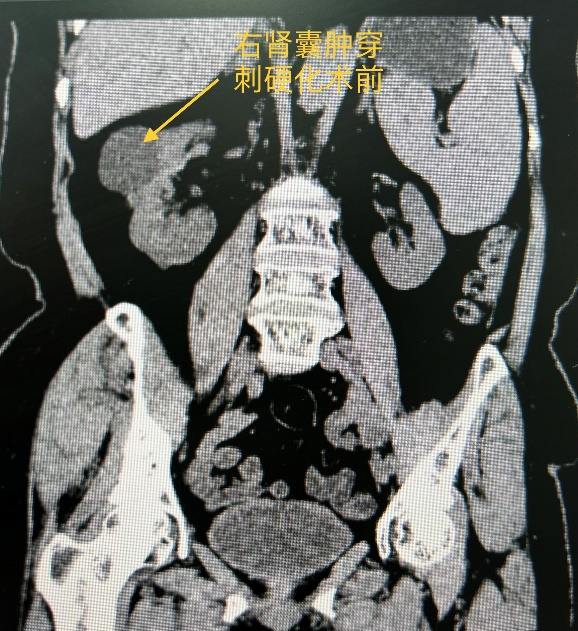

72岁的敏阿姨被腰痛症状困扰了5年,近日就诊于成人导航 肾病内科门诊,彩超提示“双肾囊性占位性病变,多考虑囊肿(右肾中极较大的54mm*45mm)”,泌尿系CT提示“双肾多发低密度病灶,考虑囊肿(右肾较大者48mm*36mm*46mm)”。经与患方沟通病情,决定行超声引导下肾囊肿穿刺硬化治疗术。

敏阿姨有高血压、糖尿病等多个慢性基础疾病,经完成充分的术前准备后,在超声科邢瑞林副主任超声引导下,由肾病内科陶小红副主任医师成功为敏阿姨实施肾囊肿穿刺硬化治疗术,术中抽出50ml囊内液体,并注入聚桂醇硬化剂,手术全程约半小时。手术后,敏阿姨觉得困扰她5年多的腰痛症状明显缓解,对治疗效果非常满意,术后次日出院回家。